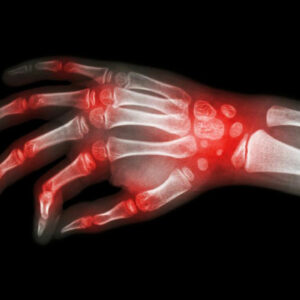

Rheumatoid arthritis and lupus – what makes them similar?

Lupus and rheumatoid arthritis are both autoimmune conditions that are often confused to be the same. The fact that these – rheumatoid arthritis, lupus are autoimmune diseases makes their symptoms similar too. Auto immune diseases are typically those conditions where the immune system of the body attacks healthy cells, causing inflammation, swelling, and pain in the affected areas.